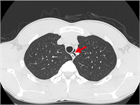

1. 若年でやせ型の男性の胸痛では、特発性縦隔気腫を鑑別診断に挙げることを勧める(推奨度2)

1. 縦隔気腫の誘因となるようなエピソードの後や原因となるような疾患を持つ症例で、胸痛や息切れ・呼吸困難などの症状がみられた場合には、縦隔気腫を鑑別に挙げることを勧める(推奨度2)

1. 胸部X線写真(CXR)で検出しきれない特発性縦隔気腫が少なからずあるため、CXRが正常範囲と判断されても、特発性縦隔気腫が疑われる場合は、積極的に胸部CTを撮影することを勧める(推奨度2)